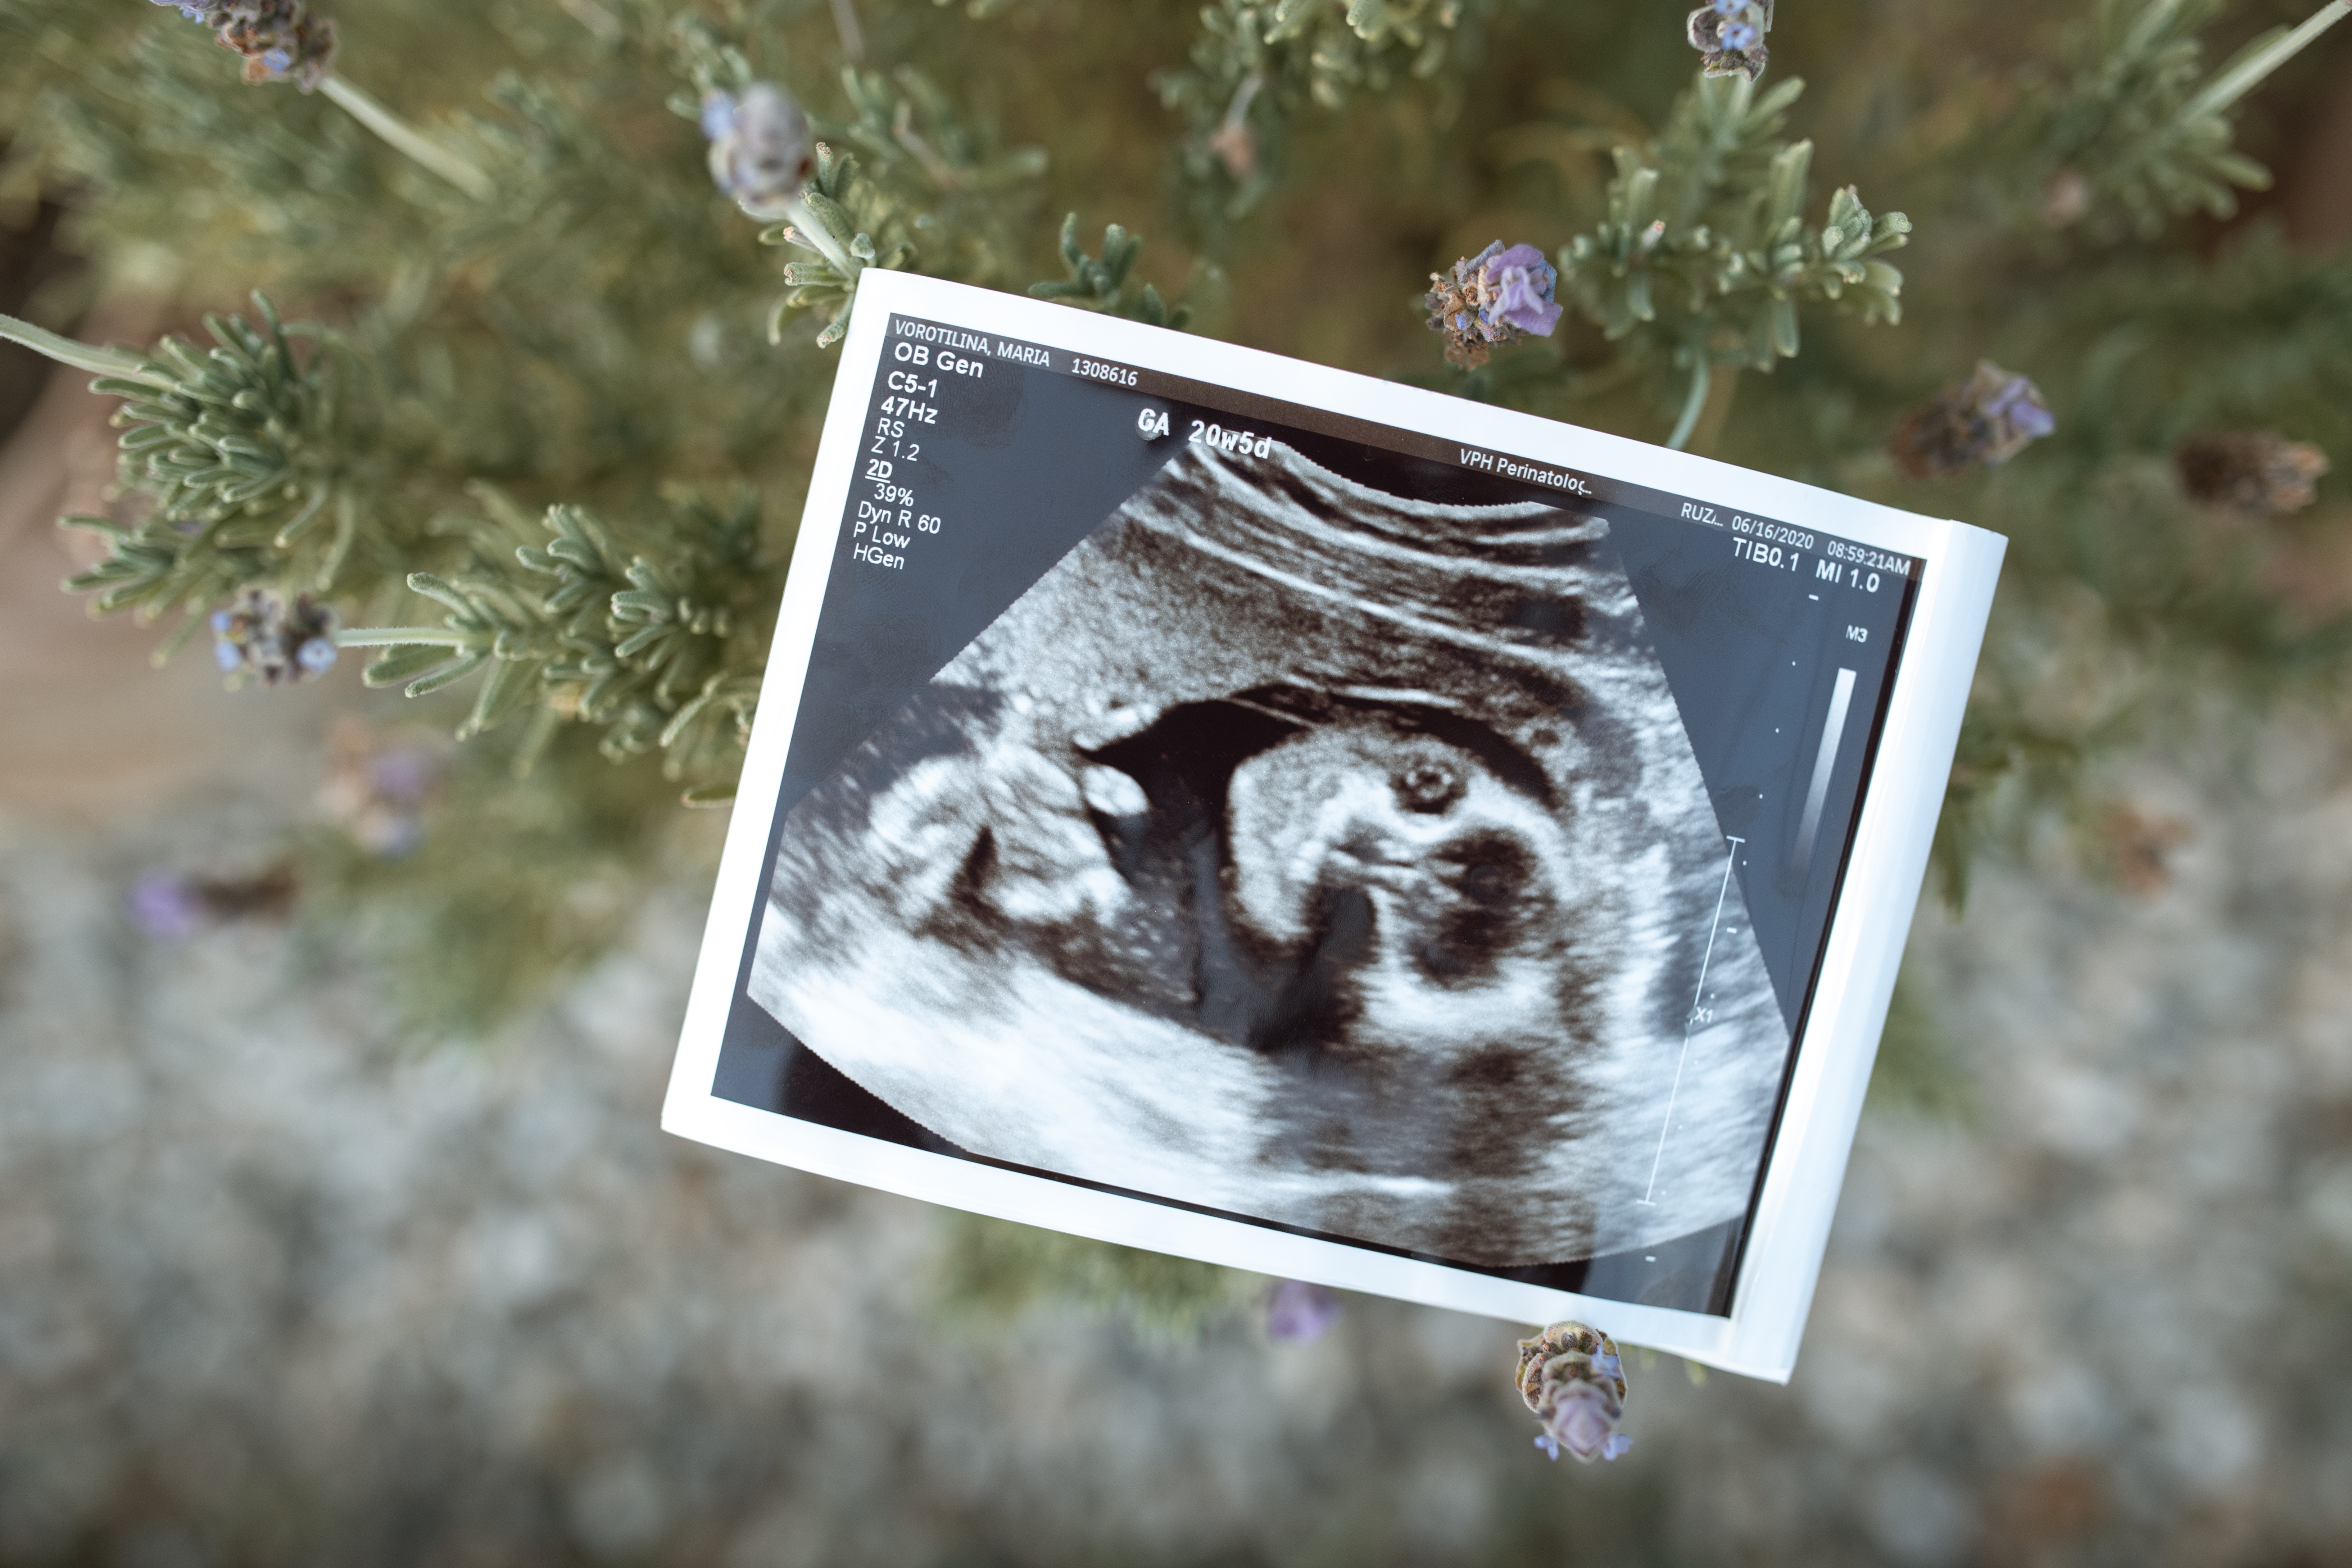

Afin de diagnostiquer le diabète gestationnel, Christelle Faubet vous propose une série d’examens médicaux tels que des tests sanguins pour mesurer le taux de glucose à jeun et 2 heures après un repas.